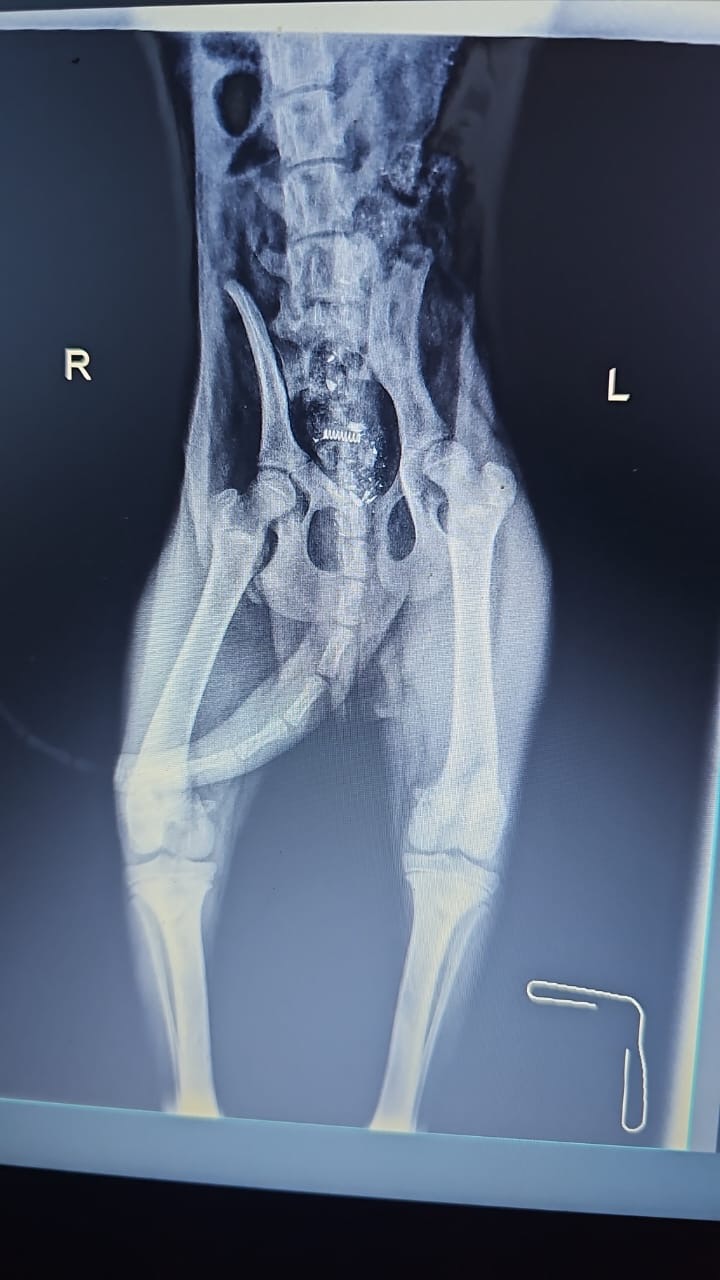

Vaila was rescued from Sawfar. She was shot, had an ulcer in her left eye, entropy on, mammary gland tumors and deformed leg. Skin infection due to fleas infestation. . She’s very sweet, calm and good with dogs. DOB: 9/9/2013